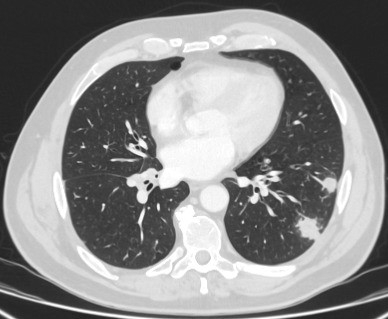

Computed tomography (CT) showing a right upper lobe apical solid nodule with a surrounding ‘ground glass’ halo, in a patient with seropositive rheumatoid arthritis on methotrexate. Other similar nodules were seen throughout both lungs, and remain stable for >2 years, consistent with inflammatory benign rheumatoid nodules

From the collection of Dr George Tsaknis, MD, PhD, FRCP(London), MRQA, MAcadMEd, PGCert; used with permission